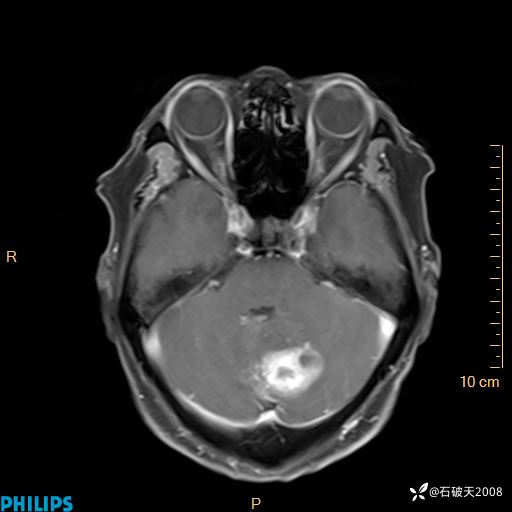

T2

T1